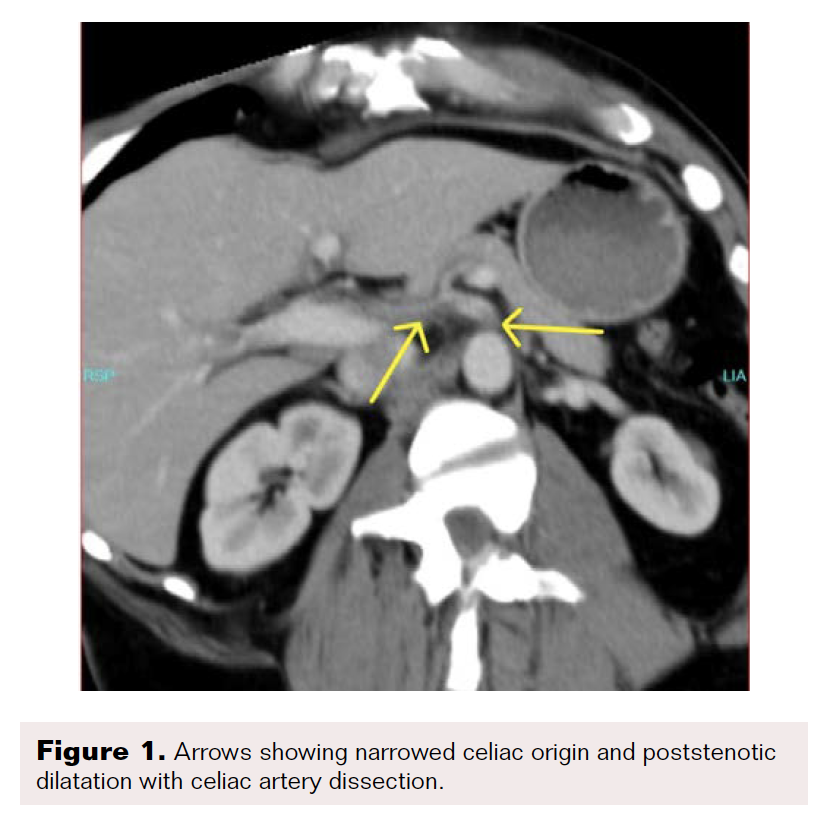

A contrast-enhanced CT scan was completed and revealed stenosis of the celiac trunk and mild bulbous dilatation of the post-stenotic celiac trunk (Figure 1). There was the appearance of a dissection flap that developed into an eccentric hypodense non-enhancing false lumen. This appeared to extend into the common hepatic arterial trunk and the splenic arterial branch, then continued to the splenic hilum (Figure 2 and Figure 3). In addition, there was a large splenic hypo-density involving almost one-third of the central spleen (Figure 4). The findings were consistent with an acute dissection of the splenic and hepatic arteries, along with splenic infarction of the central one-third of the spleen. A differential diagnosis of arcuate ligament syndrome was also considered, given the significant scoliosis seen on scout film of the CT scan (Figure 5).

The patient was treated conservatively with analgesia, blood pressure control, and anticoagulation. A follow-up CT scan 3 days later, confirmed the arterial dissections. He was discharged after 3 days of hospitalization, with a follow-up abdominal duplex ultrasound planned for 1 month. The arterial duplex scan at 1 month revealed a celiac artery peak systolic velocity > 3.5 and good intraluminal color filling without obvious evidence of a dissection or false lumen. The spleen demonstrated findings suggestive of an evolving infarction.